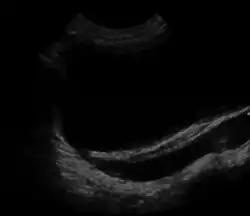

Ultrasound Scan -Vesicoureteral reflux

MCDK is usually diagnosed by ultrasound examination before birth. Mean age at the time of antenatal diagnosis is about 28 weeks[3] A microscopic analysis of urine in individuals with probable multicystic dysplastic kidney should be done.[4] One meta-analysis demonstrated that unilateral MCDK occurs more frequently in males and the greater percentage of MCDK occur on the left side of the body.[11]